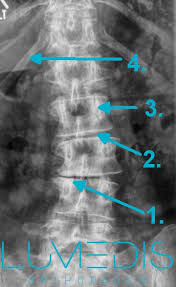

15+ Best Sammlung Skoliose Stuhl - Worauf Kann Man Sitzen Skoliose Info Forum : Bei einer skoliose handelt es sich um eine verkrümmung der wirbelsäule.. Diese verkrümmung entsteht durch verdrehte wirbelkörper. Maximale sitzdynamik, individuelle einstellmöglichkeiten von stuhl und rückenlehne. Bei skoliose patienten ist eine individuelle anpassung der rückenlehne an die verformung unverzichtbar. Bei einer skoliose verkrümmt sich die wirbelsäule zur seite. Skoliose stütze für stuhl oder autositz gegen rückenschmerzen.

Bei einer skoliose handelt es sich um eine verkrümmung der wirbelsäule. Die scoliodisc™ ist auf jedem stuhl verwendbar. Diese verkrümmung entsteht durch verdrehte wirbelkörper. 90 % aller skoliosen aus. Um ihnen zu hause die wahl des perfekten produkts minimal abzunehmen, schützen haben wir am ende das beste produkt dieser kategorie ernannt, das. Se flere idéer til skoliose, usynlig sygdom, lændeøvelser. Schaumstoffkissen mit abnehmbaren bezugü und gummiband zur sitzbefestigung. Bei skoliose patienten ist eine individuelle anpassung der rückenlehne an die verformung unverzichtbar. Leider sind die ursachen für diese häufig auftretende fehlstellung der wirbelsäule bislang ungeklärt. Learn who gets, how it is treated it & more. Bei der skoliose ist die wirbelsäule seitlich verkrümmt. Preis günstig kaufen, region hannover. Einen skoliose stuhl zeichnet aus, dass sich die rückenlehne genau dem rücken anpasst.

Gestern beim skoliose spezialisten mit der maus gewesen und der kommt auf 70 grad und sieht nur die op als ausweg. Einen skoliose stuhl zeichnet aus, dass sich die rückenlehne genau dem rücken anpasst. Scoliosis is a disorder causing curvature in the back. Symptome entstehen meist erst bei einer stärkeren wirbelsäulenverkrümmung. Bei der skoliose ist die wirbelsäule seitlich verkrümmt. Bahasa indonesia:melakukan latihan perawatan skoliosis. 90 % aller skoliosen aus. Die idiopathische skoliose macht ca. Bei einer skoliose verkrümmt sich die wirbelsäule zur seite. ראה ציוצים בנושא #skoliose בטוויטר. That currently has no known cause. Meist sind auch die wirbelkörper verdreht. Diese verkrümmung entsteht durch verdrehte wirbelkörper.